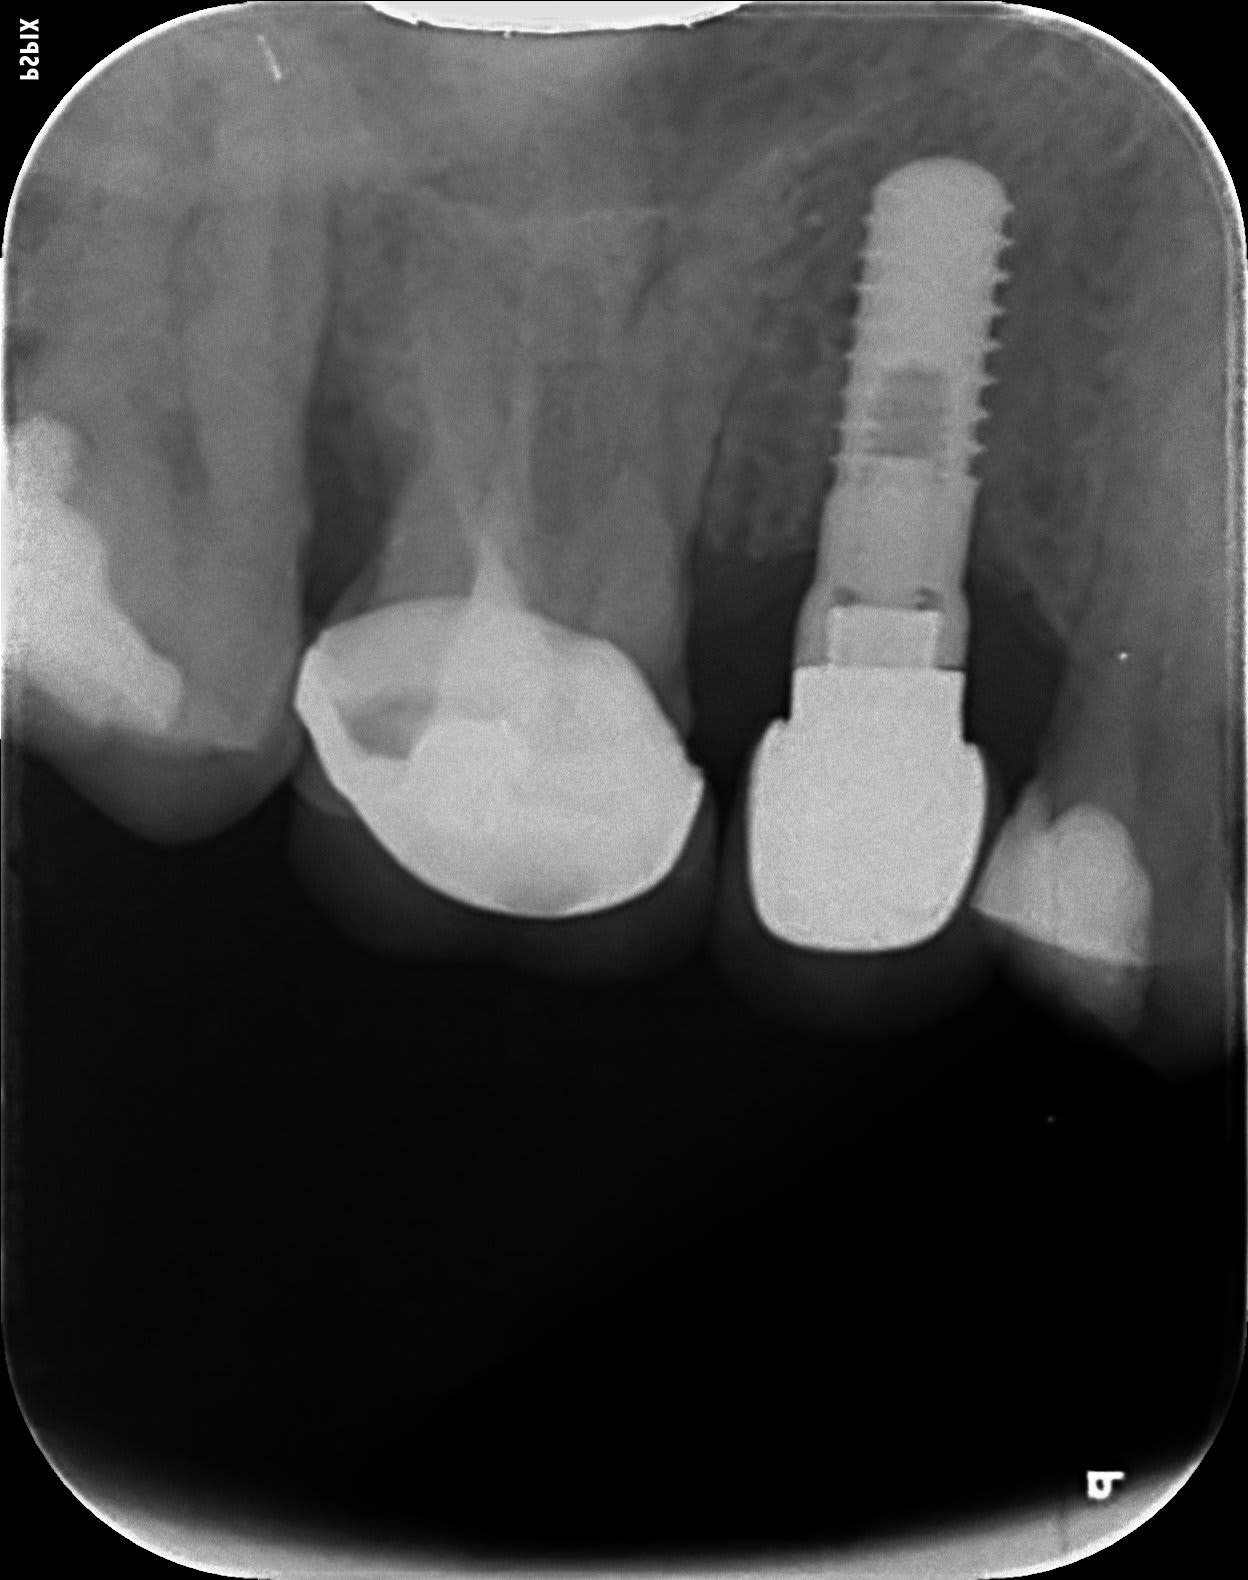

Quel est la marque de cet implant, posé aux dires du patient, il y a une 20aine d'années. J'ai été voir sur le site whatisthatimplant mais je reste à 300 résultats avec les filtres, on peut voir s'il y a un traitement de surface avec la rétro ?

https://www.spotimplant.com/fr/implants-dentaire/idi-dental/onb